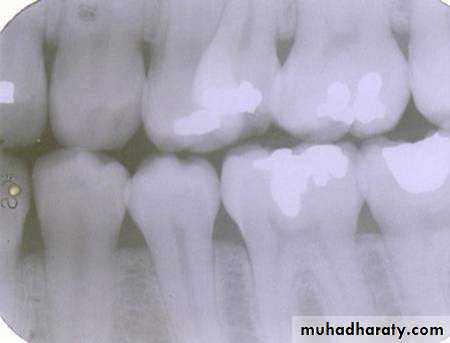

premolar filmThe arrow in the canine film is pointing to the gutta percha in which canal of the maxillary first premolar?

The arrow identifies the lingual canal. The tube head moves mesially from the premolar film to the canine film (beam directed more distally) and the gutta percha indicated by the arrow also moves mesially. (See following slide).

lingual

buccalWhen the tube head is moved mesially, with the beam directed distally, the two canals, which are initially superimposed (premolar periapical above) will separate. The lingual canal (red arrow) will follow the tube head movement and the buccal canal (blue arrow) will move in the opposite direction, as seen on the canine film.